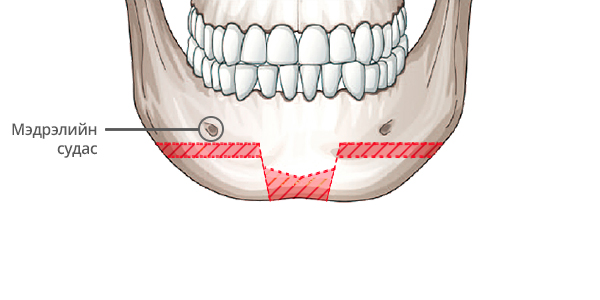

Step 1

Мэдрэлийн судсыг тойруулж, эрүүний төгсгөл хэсэгт зүсэлт хийнэ